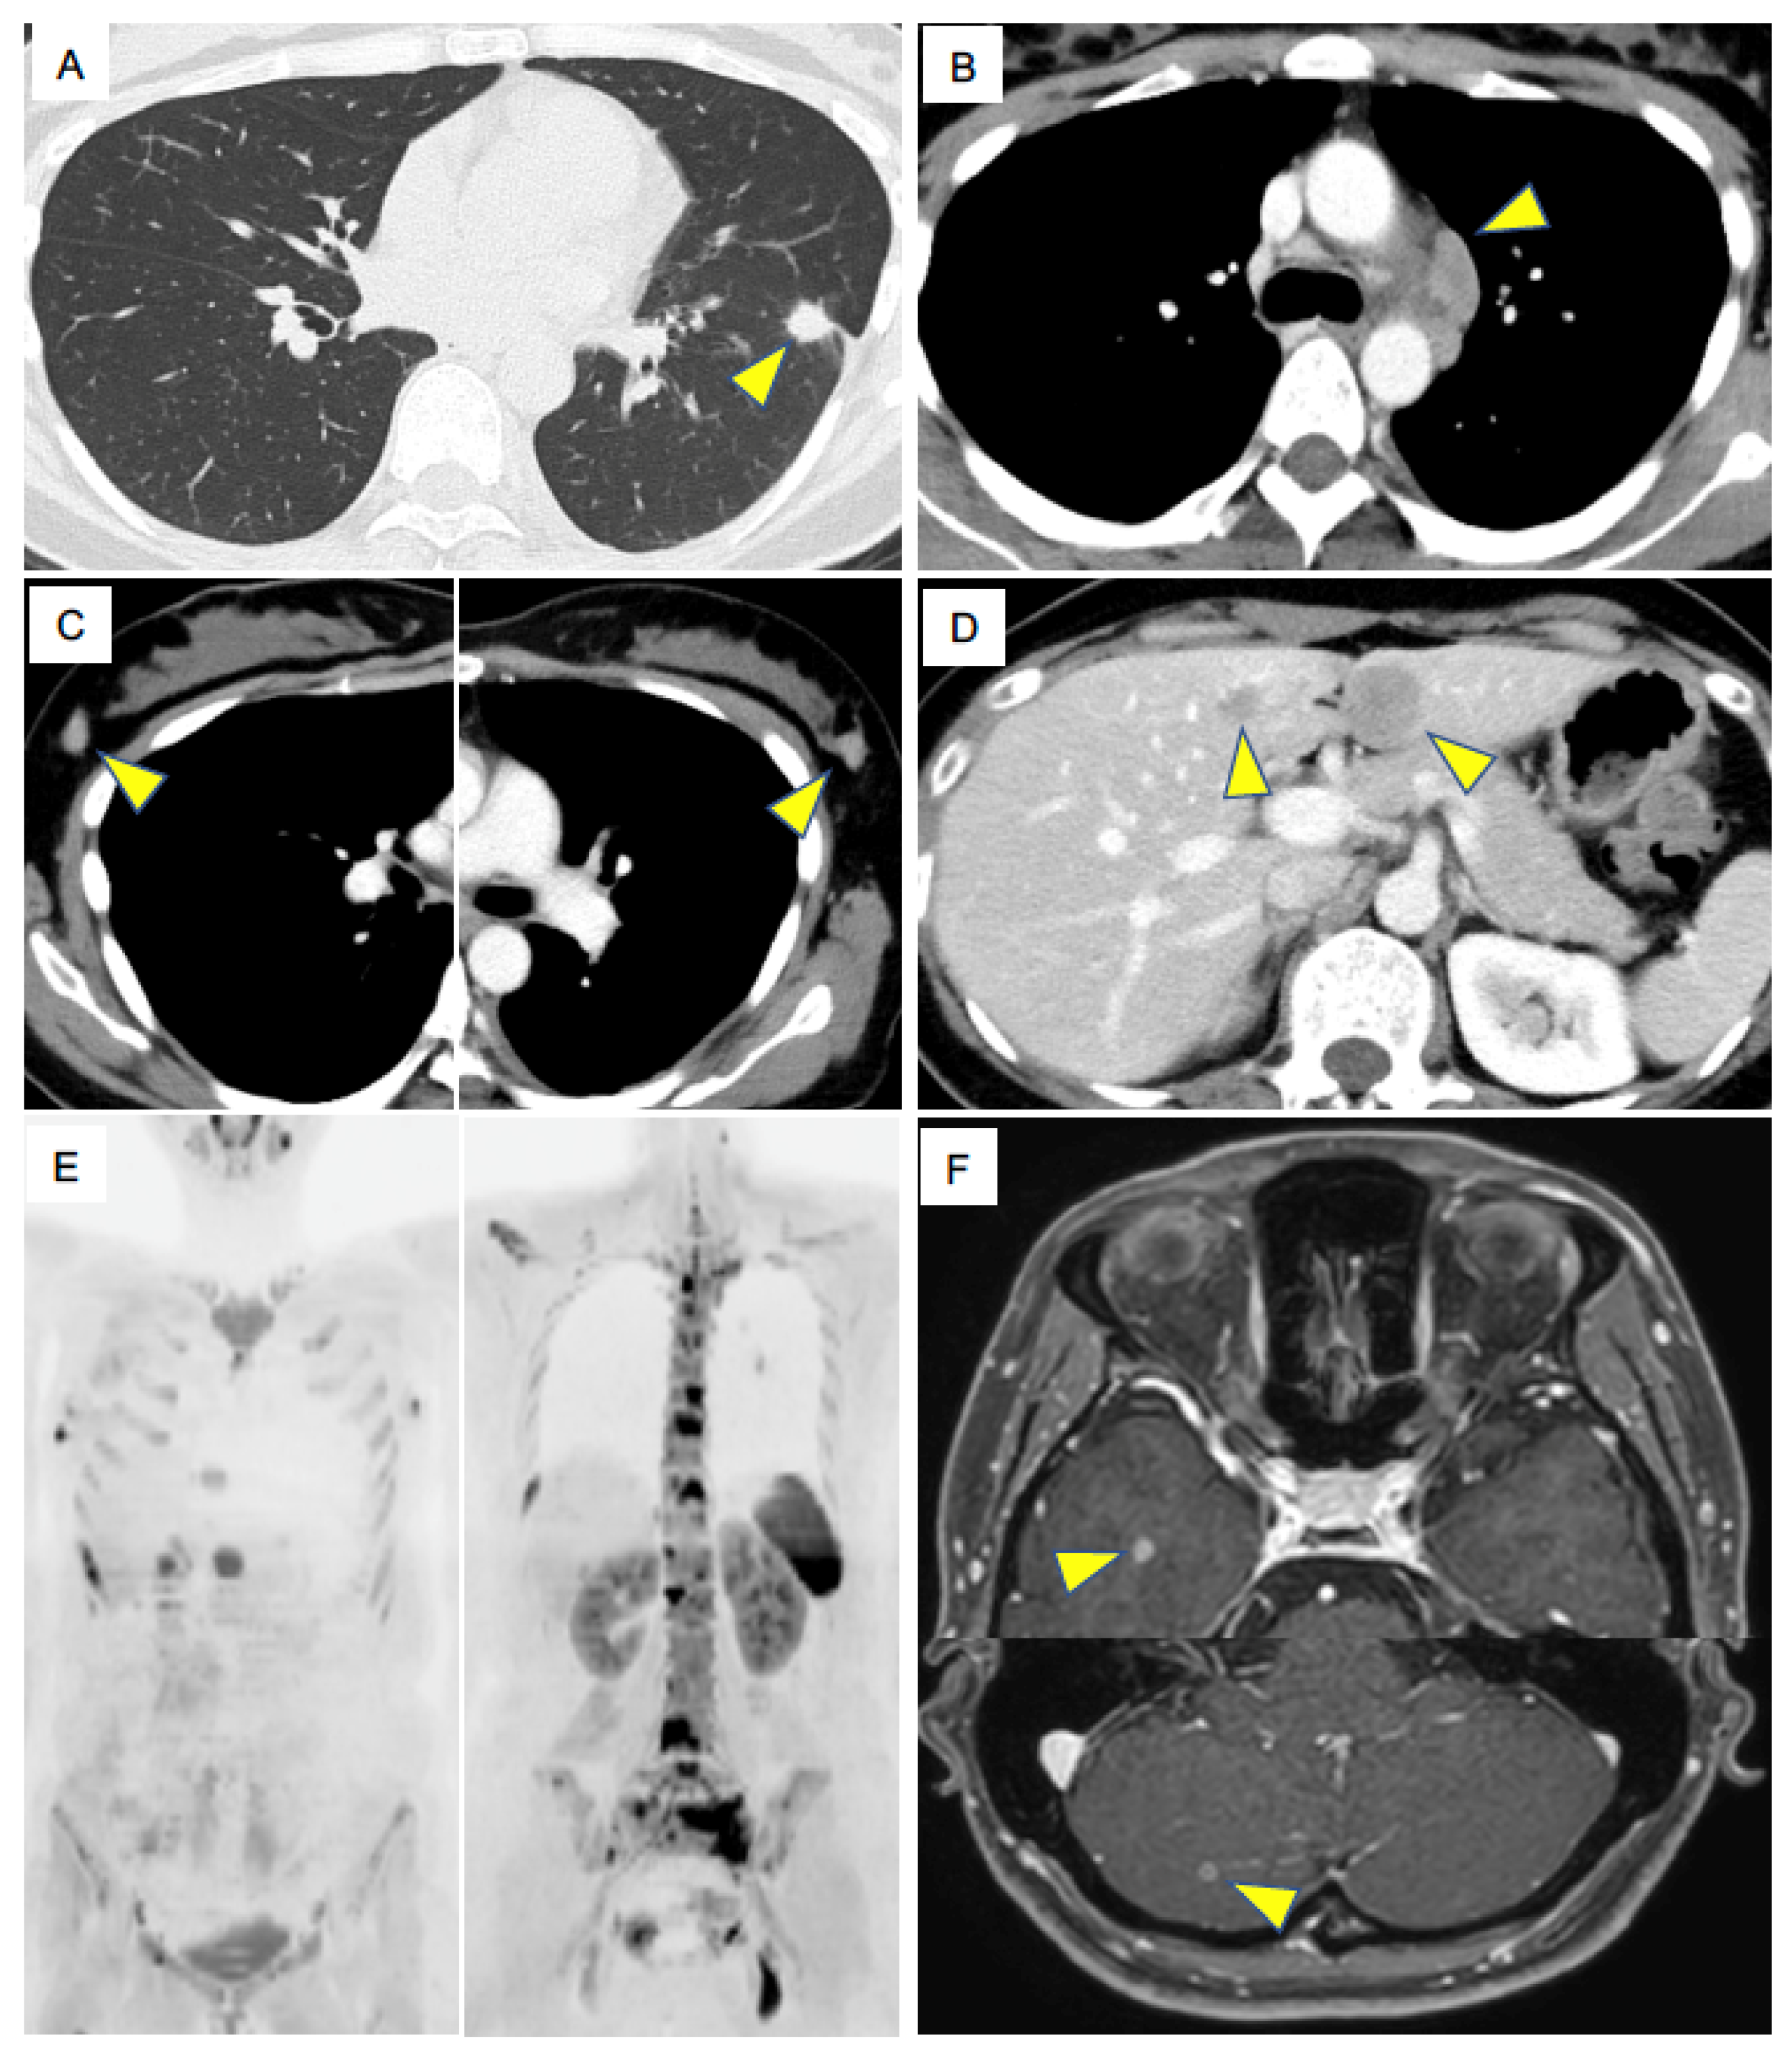

A 32-year-old woman visited our hospital complaining of low back pain. She had a three pack-year history of cigarette smoking. Contrast-enhanced computed tomography (CT) revealed multiple osteolytic changes in the vertebral bodies, nodules in the left lower lung (Figure 1A), mediastinal lymph node (LN) enlargements (Figure 1B), bilateral breast tumors (Figure 1C), and multiple tumors in the liver (Figure 1D). The patient showed rapid progression of tumors and her performance status was two. Diffusion-weighted imaging of whole-body magnetic resonance imaging (MRI) revealed multiple abnormal signals in the rib, pelvis and vertebral bodies, which indicating multiple bone metastasis, in addition to the left intrapulmonary nodules, mediastinal lymph nodes and bilateral breast tumors (Figure 1E). Contrast-enhanced brain MRI revealed multiple, asymptomatic metastases in the brain (Figure 1F). Laboratory data demonstrated elevated tumor maker level of pro-gastrin-releasing peptide (ProGRP), 4362 pg/mL. The clinical stage was IVB (cT1bN3M1c).

Figure 1.

Key imaging results at diagnosis. (A). Chest computed tomography (CT) shows a primary lung tumor in the left lower lung. (B). Contrast-enhanced CT shows enlarged mediastinal lymph nodes (LNs). (C). Contrast-enhanced CT shows enlarged bilateral breast tumors. (D). Contrast-enhanced CT shows metastatic liver tumors. (E). Diffusion-weighted imaging of whole-body magnetic resonance imaging at the diagnosis shows multiple abnormal signals in the rib, pelvis and vertebral bodies, indicating multiple bone metastasis. Left panel also shows abnormal signals in bilateral breast tumors. (F). Contrast-enhanced brain MRI shows metastatic brain tumors. Arrowheads indicate metastatic tumors.